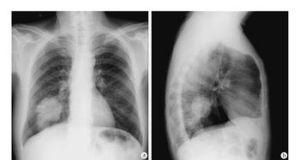

吸入較高濃度蒸氣後,很快出現流淚、咽痛、劇咳、胸悶、呼吸困難、發熱、寒戰等,脫離接觸後可逐漸好轉。少數病人經數小時至1天潛伏期後,可發生化學性肺炎或肺水腫,X線胸片示兩肺紋理模糊,散在的斑片狀或雲霧狀陰影。心電圖可見心肌損害、心率失常等。如不及時搶救,可死於呼吸衰竭。